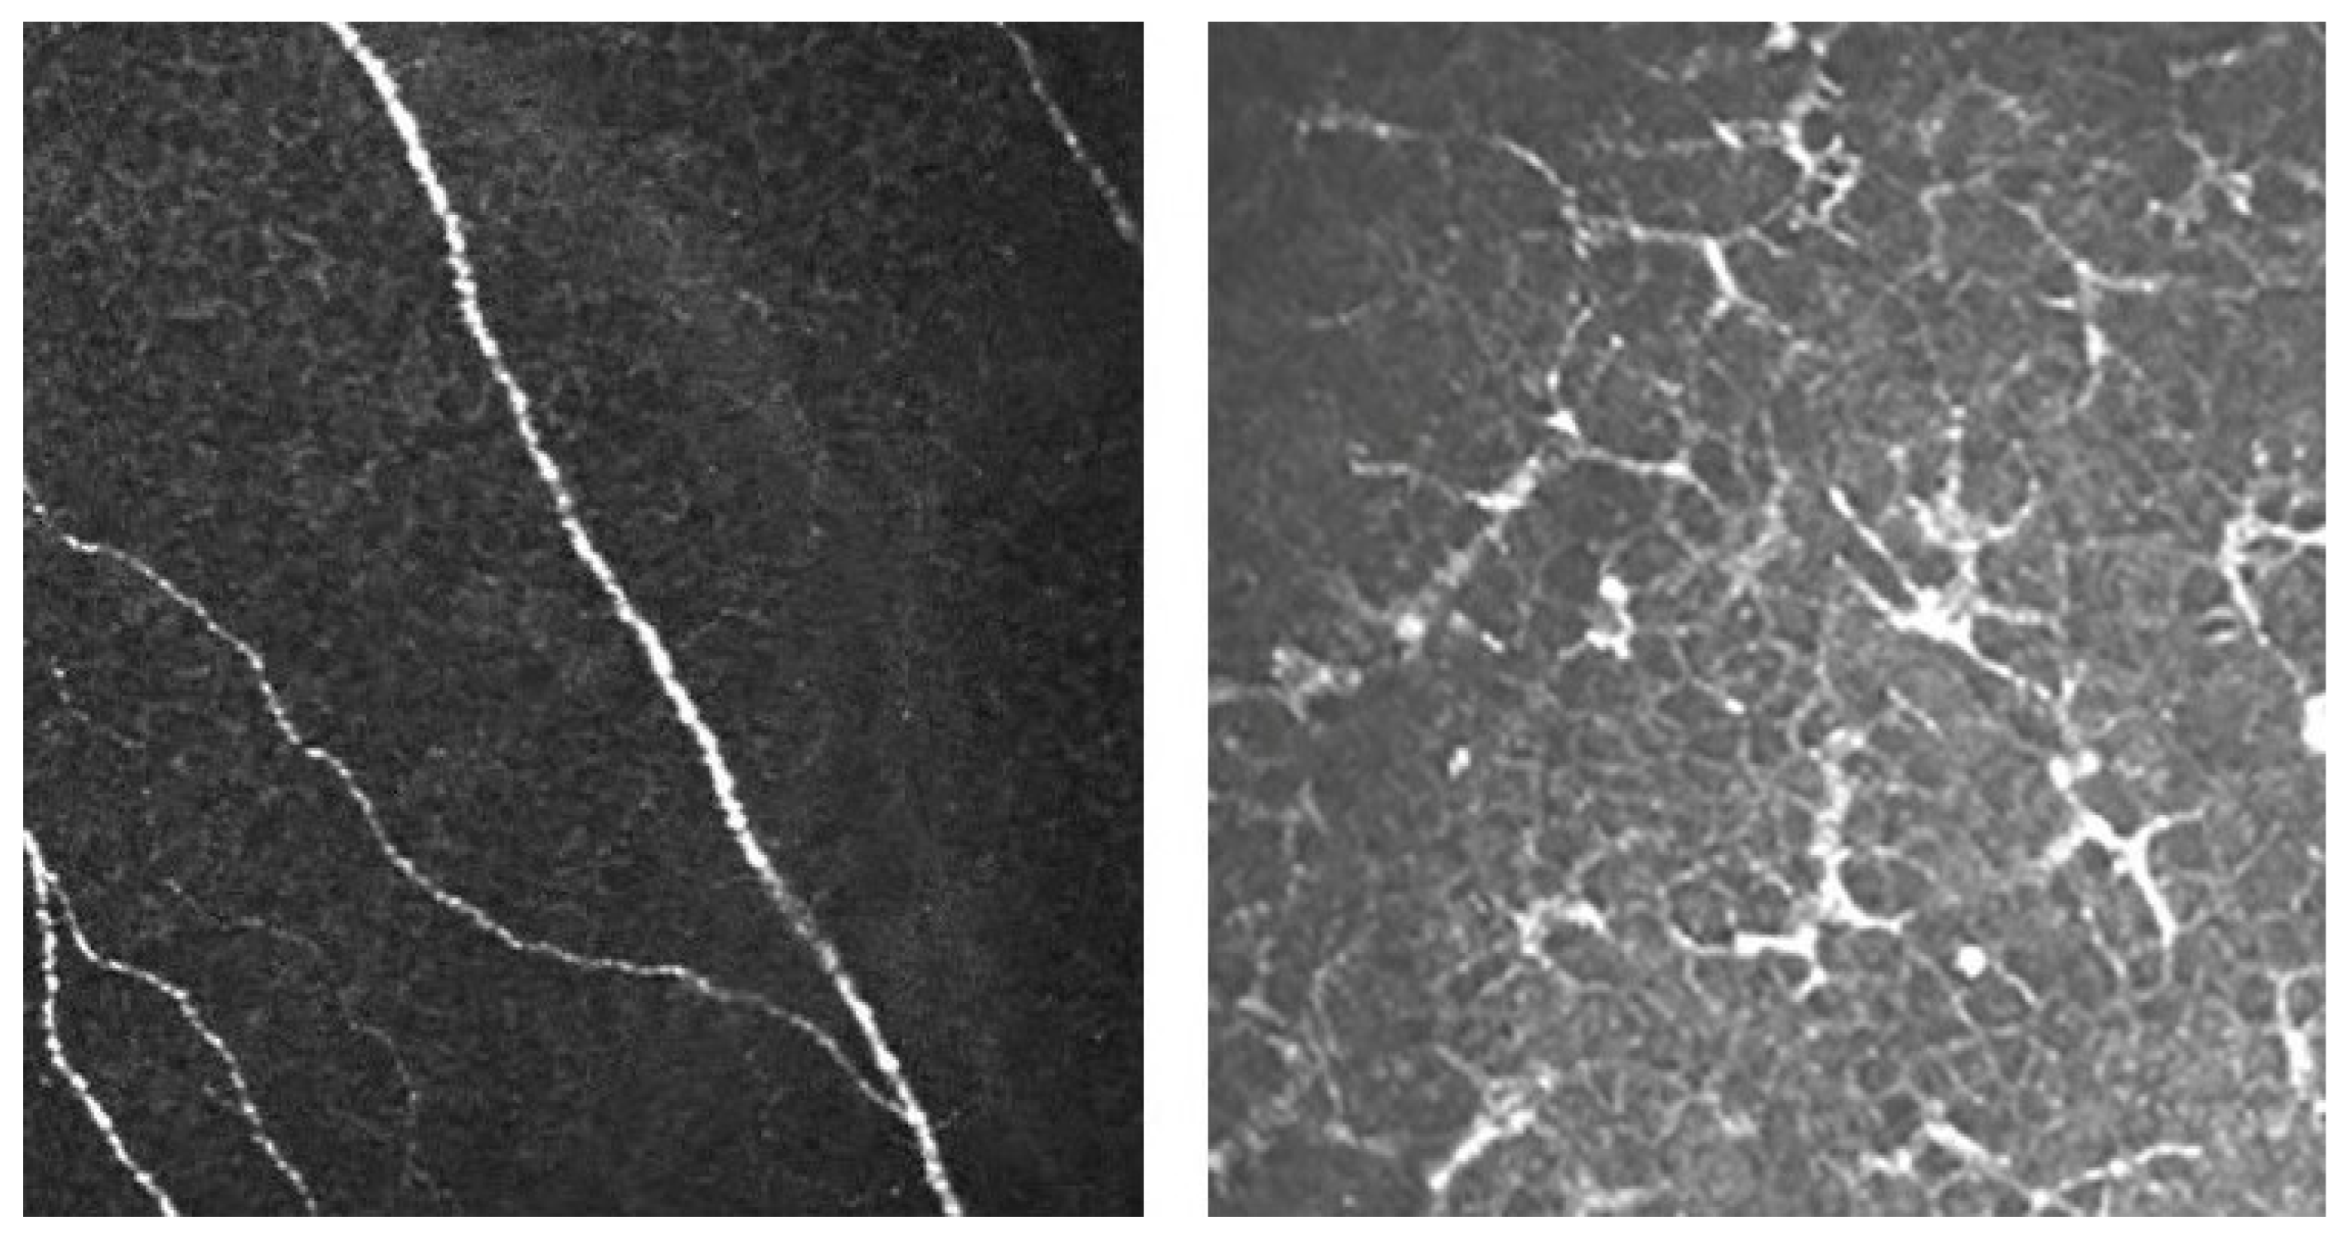

3.6. In Vivo Confocal Microscopy Clinical Applications

- Yokogawa, H.; Kobayashi, A.; Mori, N.; Sugiyama, K. Mapping of Dendritic Lesions in Patients with Herpes Simplex Keratitis Using in Vivo Confocal Microscopy. Clin. Ophthalmol. 2015, 9, 1771–1777. [Google Scholar] [CrossRef]

- Nagasato, D.; Araki-Sasaki, K.; Kojima, T.; Ideta, R.; Dogru, M. Morphological Changes of Corneal Subepithelial Nerve Plexus in Different Types of Herpetic Keratitis. Jpn. J. Ophthalmol. 2011, 55, 444–450. [Google Scholar] [CrossRef]

- Rosenberg, M.E.; Tervo, T.M.T.; Müller, L.J.; Moilanen, J.A.O.; Vesaluoma, M.H. In Vivo Confocal Microscopy after Herpes Keratitis. Cornea 2002, 21, 265–269. [Google Scholar] [CrossRef]

- Hamrah, P.; Cruzat, A.; Dastjerdi, M.H.; Zheng, L.; Shahatit, B.M.; Bayhan, H.A.; Dana, R.; Pavan-Langston, D. Corneal Sensation and Subbasal Nerve Alterations in Patients with Herpes Simplex Keratitis: An in Vivo Confocal Microscopy Study. Ophthalmology 2010, 117, 1930–1936. [Google Scholar] [CrossRef]

| Yokugawa et al. [57] | 4 | Hyperreflective irregular epithelial cells surrounded by elongated epithelial cells. Langerhans cells within the epithelium and nerve plexus |

| Rosenberg et al. [59] | 10 | Highly reflective dendritic structures in the basal epithelium |

| 19 | Alteration in the sub-basal plexus: attenuated in 9 eyes, not visible in 10 eyes | |

| Hamrah et al. [62] | 32 | Lower mean nerve density, total nerve number, main nerve trunks, and number of branches |